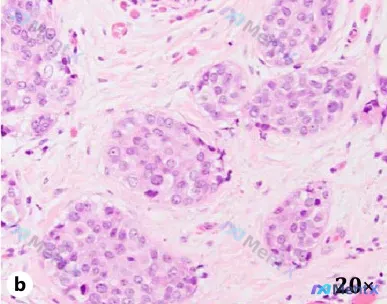

整理了一份很有代表性的乳腺病理读片思路,从HE形态到最终诊断的完整逻辑链,分享给大家: --- 病例核心信息 - 标本来源:乳腺切除组织 - 初步提示:见一灶浸润性导管癌,2级 --- HE染色(20倍)关键镜下表现 整理几个第一眼就抓住的点: 1. 生长模式:肿瘤细胞呈巢状、片状分布,大小不一,直...